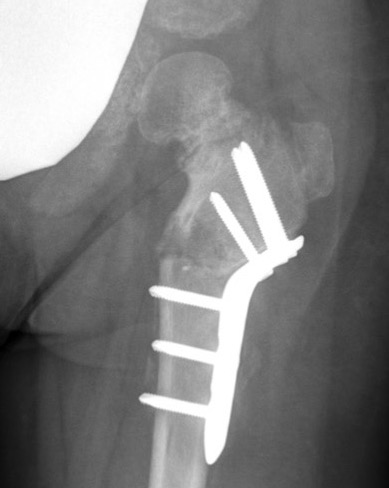

Operative management

Valgus derotation subtrochanteric osteotomy

- overcorrect to 150˚

- epiphyseal angle < 40o

- correct anteversion to 10o

Technique

Synthes Pediatric Proximal Femur Offset Plate Technique PDF

POSA proximal femoral osteotomy for coxa vara video

Lateral approach

- elevate / L shaped detachment of vastus lateralis

- mark distal and proximal with drill hole for rotation

- K wire in central head

- sub-trochanteric osteotomy with saw

- application of 150o Synthes offset locking plate

- internal rotation of about 20° at time of osteotomy